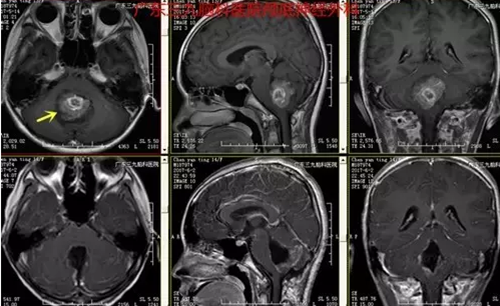

图2:术前磁共振提示肿瘤位于四脑室底-小脑蚓部、大小约3.8*2.9*3.5cm,不均匀强

本例患者为13岁11月儿童,因头痛伴呕吐入院,颅内压增高症状明显,入院时MR提示病变位于四脑室底-小脑蚓部。本例患者手术过程短,术后恢复快,未有明确并发症,术后复查头颅MR提示肿瘤全切。